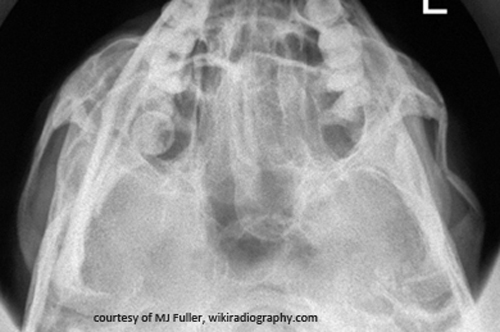

Which bones are most often fractured in facial trauma?

Mandible, maxilla, frontal bone, nasal bones, and zygoma.

Why are both sides of the mandible imaged if one side is fractured?

There is a high incidence of contrecoup fractures.

What is a major airway risk with unstable mandible fractures?

Tongue displacement obstructing the airway.